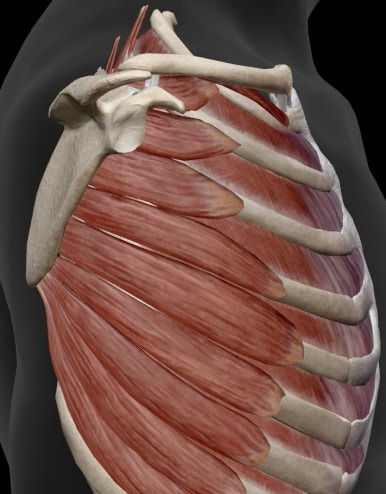

어깨뼈와 가슴우리(흉곽이) 만나는 지점이고

이름을 따라 어깨가슴 관절입니다.

어깨가슴관절은 진짜 관절이라고 하기엔

뼈와 뼈가 만나는 지점이 아니라

어깨뼈의 앞면과 가슴우리(흉곽)의

뒤쪽 가 쪽 벽 사이가 접촉되는 부위입니다.

어깨뼈와 흉벽이 직접적으로

접촉하고 있는 것이 아니라

어깨밑근, 앞톱니근, 척추 세움 근육 등에 의해 분리되어 있습니다.

사진으로 확인 후 이어서 설명드리겠습니다!

사진에 보이는 것처럼

근육에 의해 뼈와 뼈가 만나지 않고 연결되어 있으며

근육이 작용함에 따라

동작이 다양하고 크게 나타납니다!